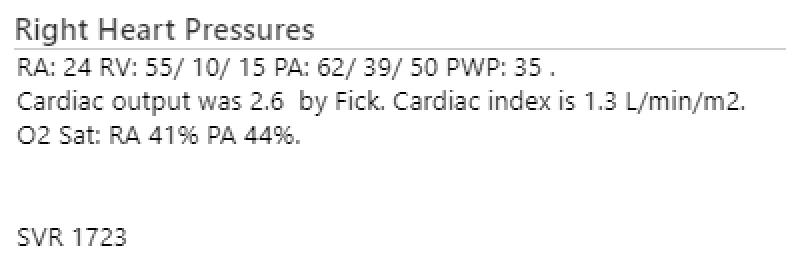

Here is a comparison⚖️of Invasive vs. Non-Invasive hemodynamics using #CrititicalCareEcho #VEXUS #POCUS

62 M/HFrEF 20% in CCU for cardiogenic shock. On 4L NC. Also + for RSV infection🫁 On dobutamine drip.

No pedal edema

JVD, Crackles, B lines +

Worsening renal function. Net -ve 10 L so far.

62 M/HFrEF 20% in CCU for cardiogenic shock. On 4L NC. Also + for RSV infection🫁 On dobutamine drip.

No pedal edema

JVD, Crackles, B lines +

Worsening renal function. Net -ve 10 L so far.